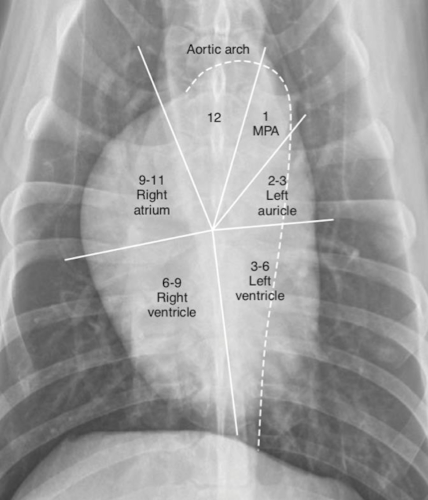

What are seen in each quadrant?

Label